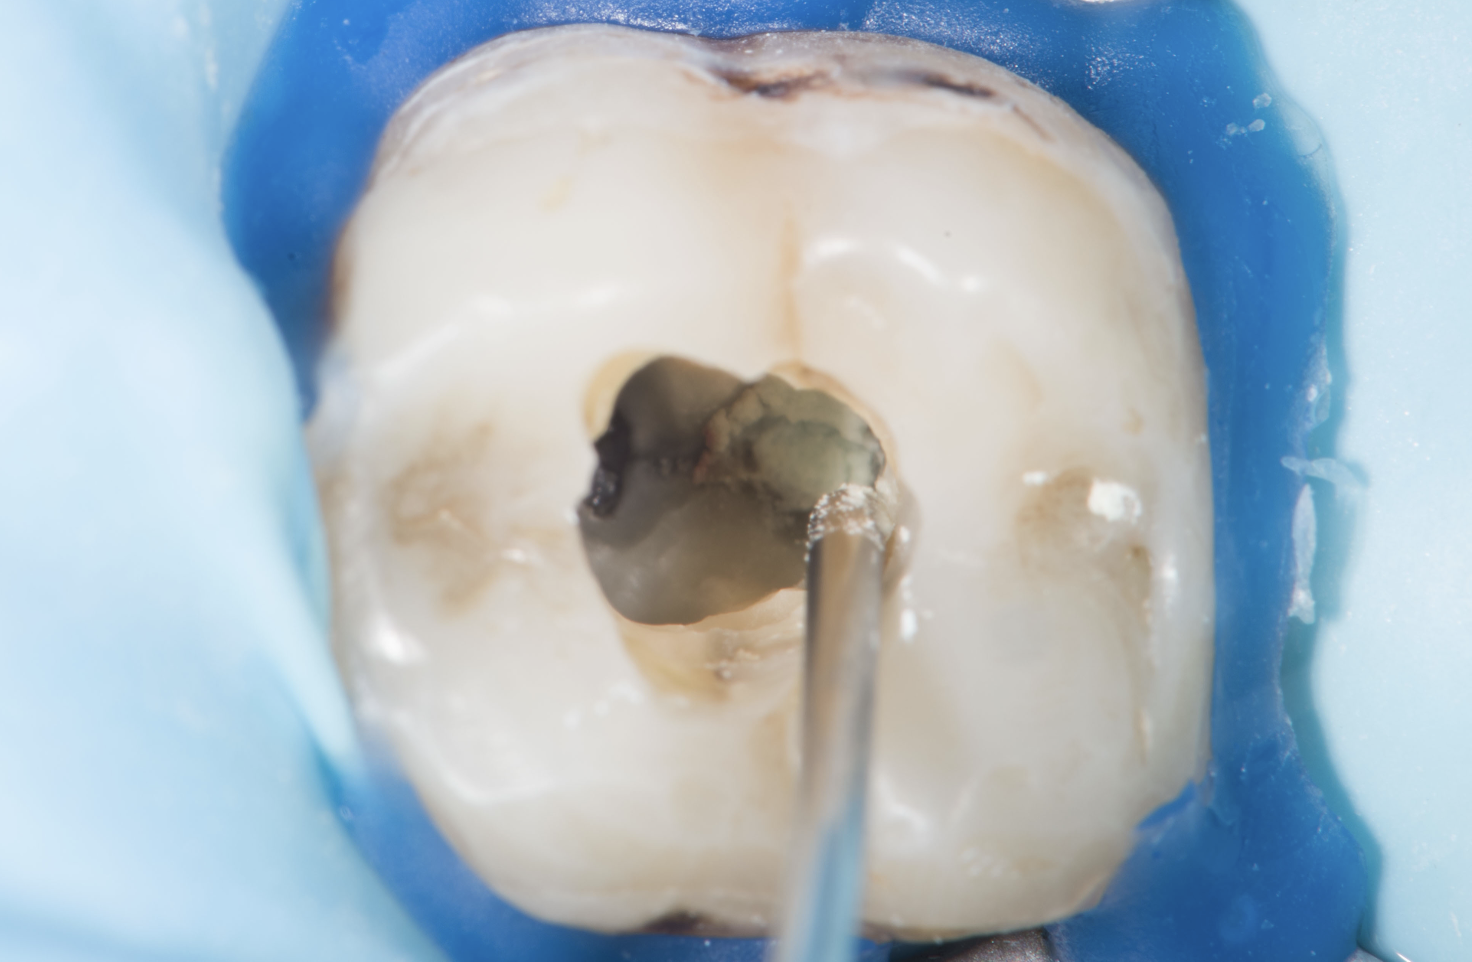

• Toepassing van pulpa-afdekmaterialen;

• Directe (diepe) adhesieve restauratie (composietopbouw);

• Materialen: calciumhydroxide, MTA, Biodentine, bioceramieken;

• De anatomie van het pulpadak en pulpakamer correct te herkennen en prepareren;

• Het juiste materiaal te kiezen voor pulpa-afdekking (zoals MTA en Biodentine);